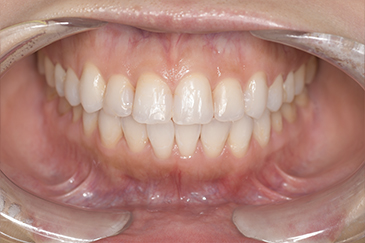

| 年齢・性別 | 52歳・女性 |

| 主訴 | クリーニングしたい |

| 治療内容 | スケーリング・PMTC |

| 治療期間 | 60分 |

| 治療費 | 約7,000円 |

| リスク・副作用 | 知覚過敏、歯肉退縮 |

| 治療方針 | 歯石とステインを除去して、今後は定期検診でのクリーニングと併せてガムピーリングやホワイトニングを行います。 |

| 担当者所見 | 歯肉の色素沈着が目立つため、ガムピーリングを行いながらホワイトニングを行うことをおすすめします。 |